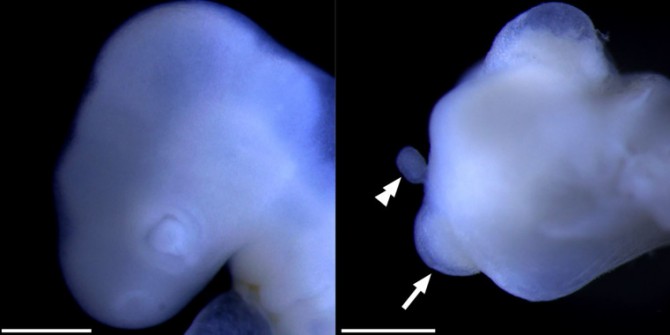

Embrión de pollo cíclope analizado en el estudio. (Foto: Paul Palmquist Gomes et al.)

Hasta el momento se han descrito diferentes formas de esta malformación. Entre estas se encuentra la aparición de un solo ojo en una órbita central o una fusión incompleta de los dos ojos en una única órbita central. En otras ocasiones sobre el ojo único puede aparecer una estructura con forma de trompa.

Finalmente, esta trompa puede surgir entre los dos ojos como si fuera una formación incompleta de la nariz e incluso en algunos casos extremos pueden llegar a aparecer dos probóscides en el lugar donde deberían estar los ojos.

Para entender el origen de la aparición de esta trompa, asociada a la ciclopía, el nuevo trabajo ha analizado un caso congénito espontáneo de ciclopía en un embrión de pollo. Los resultados apoyan los de otros muchos análisis previos que indican que esta anomalía resulta de la alteración del programa normal del desarrollo embrionario de la línea media de los organismos.

La conclusión más importante de la investigación en este caso es que la identidad celular de alguno de los tejidos faciales durante el desarrollo embrionario de la malformación es compleja.

“Nuestro análisis sugiere que en determinadas ocasiones, la base de la probóscide de este tipo de cíclopes está más relacionada con los tejidos oculares que con los tejidos nasales”, revelan a Sinc los investigadores de la Universidad de Málaga.

Por otra parte, el estudio también subraya que durante el desarrollo embrionario el ojo cíclope se asocia a los tejidos olfatorios y no a los progenitores de la retina.

El análisis en profundidad de las diferentes estructuras encontradas en este embrión de pollo cíclope puede desvelar por qué en algunos casos de individuos cíclopes, la estructura central que habitualmente se considera un ojo, carece de tejidos que caracterizan este órgano, como es el caso de la retina.